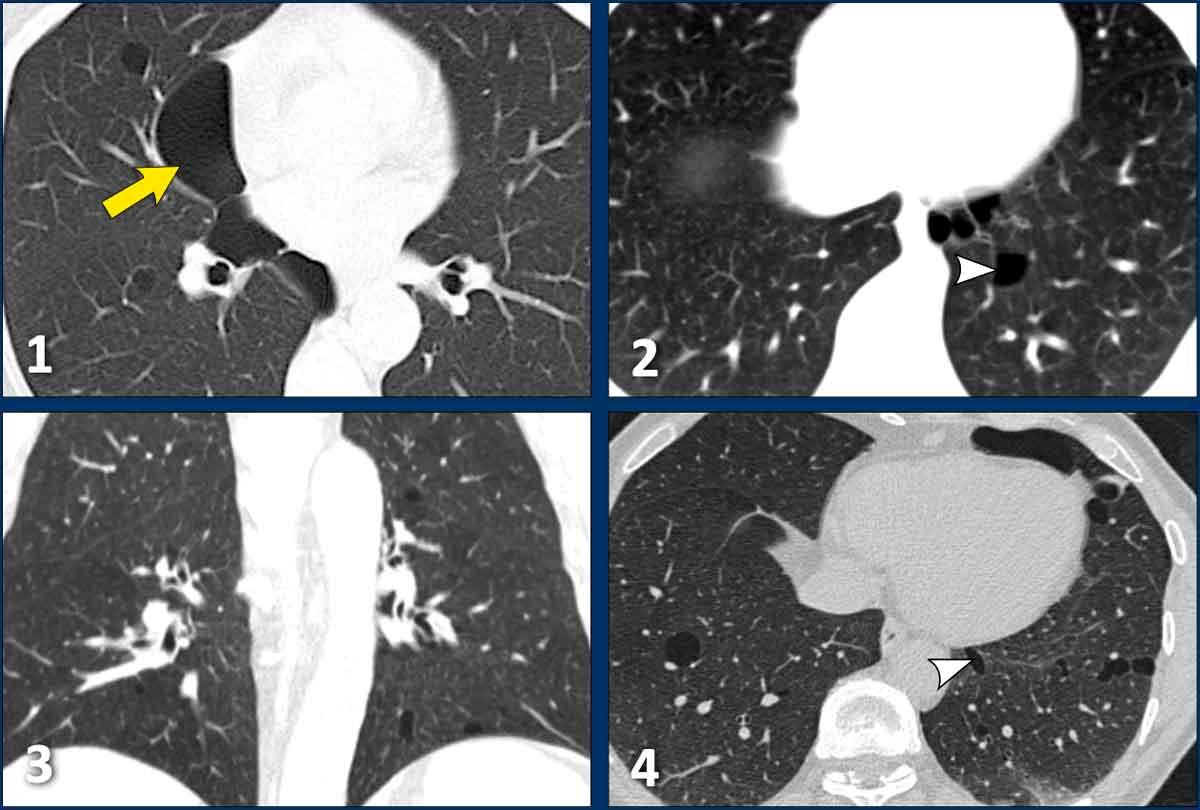

Các nang trong BHD có xu hướng phân bố ưu thế ở vùng phổi thấp và ngoại vi.

Đôi khi các nang có ranh giới được xác định bởi các vách liên tiểu thùy, tạo cho chúng hình dạng tam giác hoặc thấu kính đặc trưng (đầu mũi tên trong hình 2 và 4).

Các nang BHD không nhiều, thường ít hơn 50 nang. Đôi khi số lượng nang rất ít với hình ảnh rất tinh tế (hình 3), nhưng không được bỏ sót.

Hình ảnh

- Các nang BHD. Một số nang tiếp giáp với màng phổi (mũi tên vàng) hoặc các rãnh liên thùy. Các nang ở vùng phổi thấp cũng có thể gặp trong LIP. Khí phế thũng cạnh vách liên tiểu thùy có phân bố ưu thế ở vùng phổi trên.

- Phân bố ưu thế ở vùng phổi thấp và các nang hình tam giác (đầu mũi tên) trong BHD.

- Lưu ý hình ảnh rất tinh tế với phân bố ưu thế ở vùng phổi thấp.

- Các nang BHD điển hình

Đây là hình ảnh của một phụ nữ 56 tuổi, có tiền sử tràn khí màng phổi tái phát và hiện tại nhập viện lần này cũng vì tràn khí màng phổi (mũi tên).

Hãy phân tích hình ảnh.

Đây là các nang thực sự hay các tổn thương giả nang?

Đây là phát hiện tình cờ hay bạn cho rằng đây là bệnh phổi dạng nang?

Chẩn đoán có khả năng nhất là gì?

Nhận xét hình ảnh

Có nhiều nang thành mỏng – hơn bốn nang. Lưu ý vị trí phân bố gần các rãnh liên thùy và ở ngoại vi phổi.

Kết luận

Đây là trường hợp hội chứng Birt-Hogg-Dubé (BHD).

Bàn luận

Hai bệnh phổi dạng nang thường biểu hiện bằng tràn khí màng phổi là LAM và BHD.

LAM biểu hiện là các nang đơn thuần, thành mỏng, hình tròn hoặc bầu dục, đều đặn với phân bố lan tỏa.

Vị trí ngoại vi và cạnh rãnh liên thùy của các nang BHD thường tạo ra các góc nhọn, khiến chúng có hình dạng thấu kính.

Khi các nang có hình ảnh đặc trưng này, chúng có độ đặc hiệu cực kỳ cao cho chẩn đoán hội chứng Birt-Hogg-Dubé.